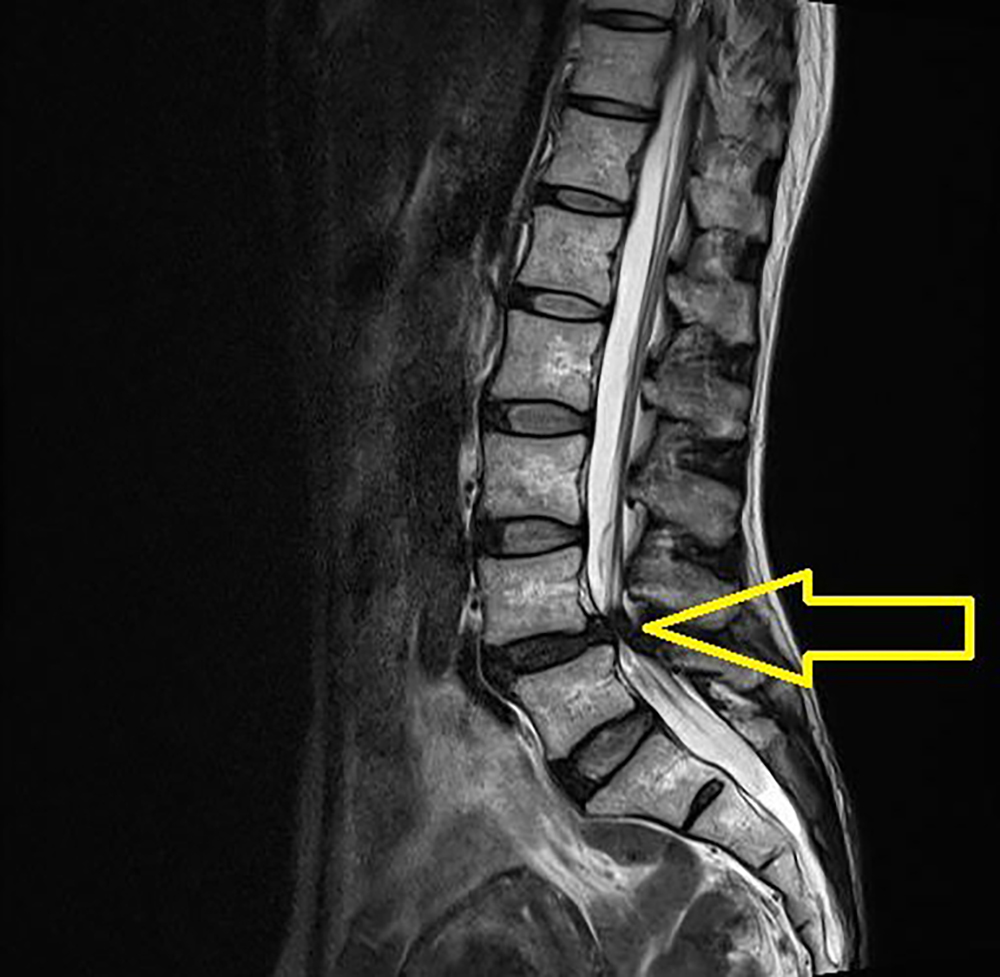

脊柱管狭窄症・膠原病など難病も漢方で治癒する

脊柱管狭窄症(せきちゅうきょうさくしょう)は腰から下の神経に関連する症状、具体的には、腰の痛み、臀部の痛み・しびれ、足の痛み・しびれ、足の筋力低下、歩行障害、排尿障害などが表れる。

西洋医学では消炎鎮痛剤、神経ブロック注射、外用剤(湿布薬.貼り薬・塗り薬)など対症療法か、症状がひどい場合は手術をする。

しかし、手術しても痛みが取れない場合も多々ある。

中国伝統医学では、この病気の原因は脊柱管近くの浮腫、炎症、血流障害、骨の老化(五臓のうち腎の異常) などが複合的に重なって引き起こされることが多いと考え、浮腫や、炎症、骨の老化や血流障害を改善する生薬などを組み合わせた処方をすれば症状は消失する。